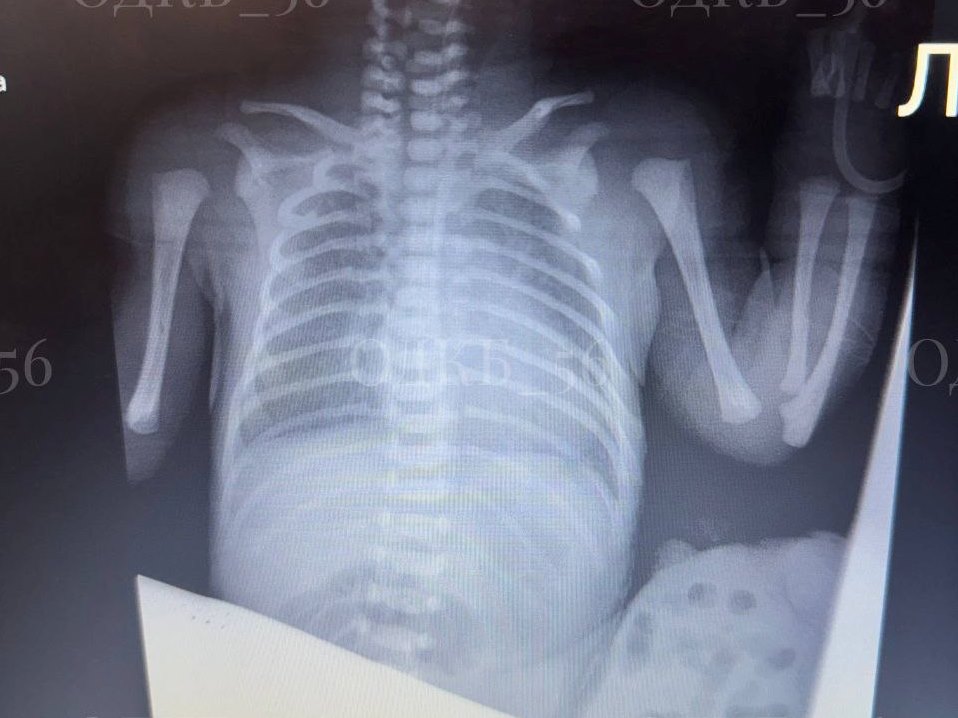

В областную детскую клиническую больницу поступил новорожденный пациент с омфалоцеле. Грыжа пупочного канатика имела довольно большой размер. Хирурги приняли решение оперировать.

Омфалоцеле – это довольно редкая врожденная патология, при которой внутренние органы, чаще всего печень и кишечник, выходят за пределы брюшной полости и попадают в пуповину, формируя «мешочек». Такая патология встречается от 1 до 5 случаев на 10 000 новорожденных.

Сразу после подготовки младенцу провели операцию. Бригада детских хирургов устранила дефект, вернула внутренние органы в брюшную полость и выполнила пластику, сформировав из собственных тканей ребенка пупок. Операция прошла благополучно.